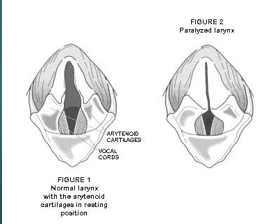

Laryngeal paralysis

Loss of motor function of the larynx

Causes a narrowing of the larynx so is harder for their air to move through

Most commonly seen in large breed dogs

Laryngeal paralysis can be caused by ..

Polyneuropathy

Trauma

Iatrogenic - neck surgery

Hypothyroidism

Neoplasia - mass on the larynx or on the nerve

Polyneuropathy